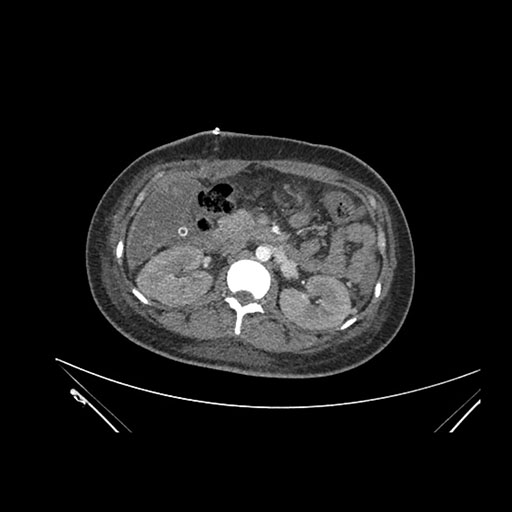

Imaging Analysis

Look through the patient's CT scan to identify any areas of concern for the necessary procedure.

Axial Venous

Based on initial findings, which issue(s) would you be most concerned about?